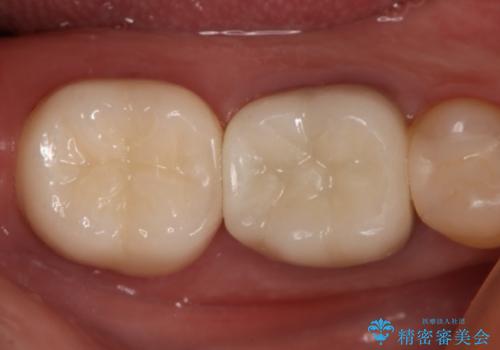

痛みは完全に取り除かれ、咬合時の違和感もなく経過は良好です。

セラミックでの治療を希望されたので補綴はオールセラミッククラウンでの治療を選択しました。